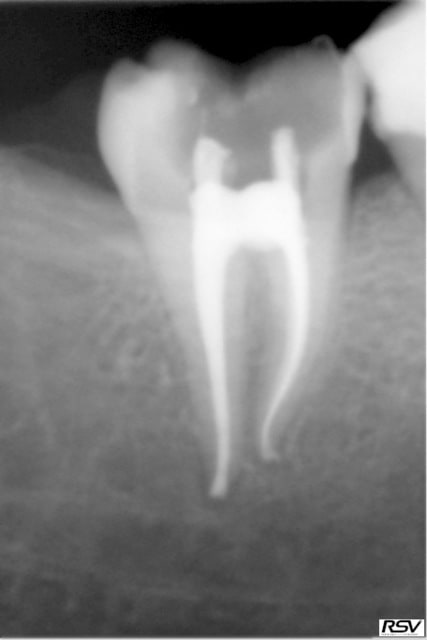

pour être sincère adhoc, a la premiere radio l'opacité du tenon m'a si peu marqué que je ne l'avais pas vu:)

Curieux, mon athos, les tenons carbonne sont moins opaques aux RX, d'habitude! ; cela dit, je trouve ta radio tres bien, peut etre qu'en étant puriste, il faut adapter en rendant paralleles l'axe de la dent et l'axe principal -ici vertical-, mais ne chipotons pas, je serais incapable de faire mieux, sauf coup de chance!)